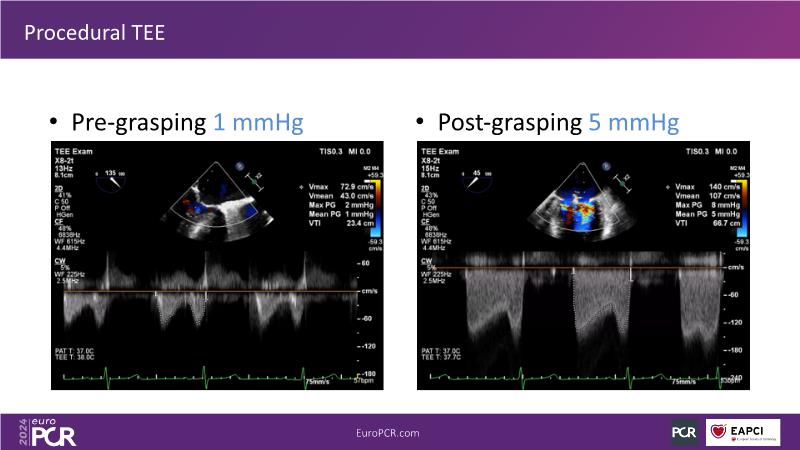

Watch this session to gain insights into the clinical evidence of mitral TEER therapy for the Asian population, learn techniques for implanting a MitraClip in patients with challenging anatomy, and understand how to use the four clip sizes for optimal outcomes. The session also covers educational aspects of clipping in dextrocardia, the benefits of reserve bending of the transseptal needle for tenting and puncture, new steering maneuvers for dextrocardia patients, and the importance of understanding anatomy and collaborating closely with the echo team for success.